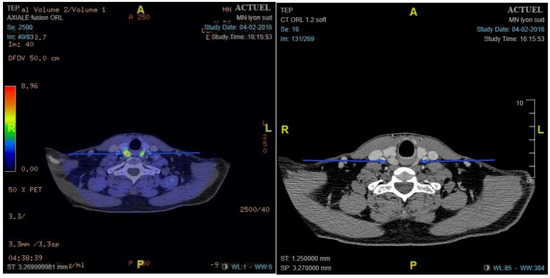

- Preoperative 18F-choline PET/ceCT data: lesion location, number of lesions, lesion size, and maximum standardised uptake value (SUVmax)

2.3.1. 18F-Choline PET/ceCT Protocol